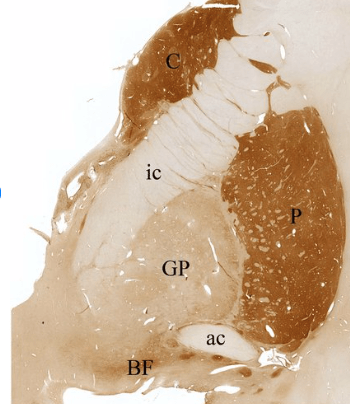

Figure 2. Coronal section of the brain of a 66-year old healthy female at the level of the anterior commissure (AC) showing part of the basal ganglia, stained for acetylcholine-esterase. Bridges of persistent gray matter in the internal capsule are the cause of the striate’s striped appearance. The part of the pallidum under the anterior commissure is called the ventral pallidum.

From: Jarret P, Easton A, Rockwood K et al Evidence for Cholinergic Dysfunction in Autosomal Dominant Kufs Disease Can J Neurol Sci 2018; 45(2): 150-157 doi: 10.1017/cjn.2017.261